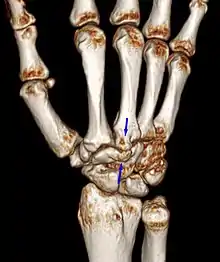

Carpal boss VR-3D-Reconstruction

The carpometacarpal joint is usually found at the base of the second and third metacarpal bones at the point where they meet the small bones of the wrist.[2]